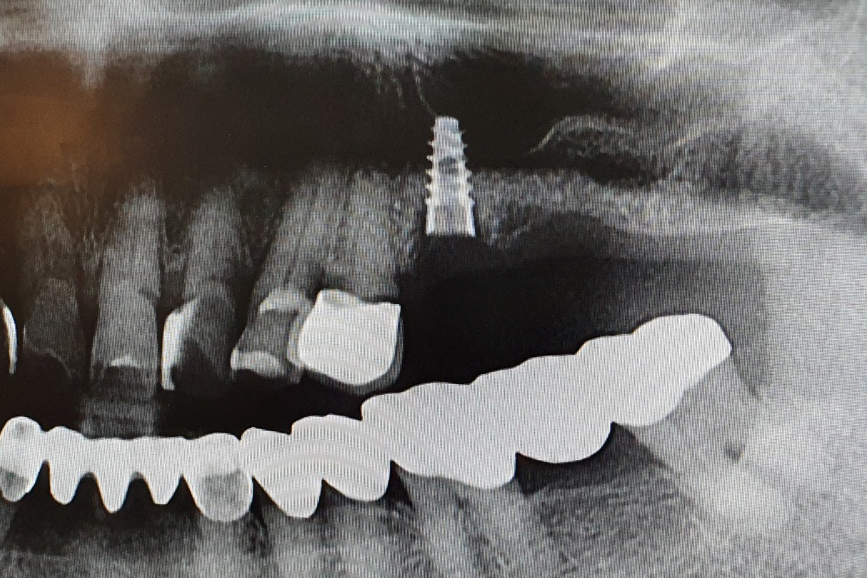

신논현역 치과 스마일 뷰는 부모님 임플란트를 더욱 정확하게 시술하기 위해서

내비게이션 임플란트 방식을 진행하고 있습니다.

내비게이션 임플란트로

안전하게!!

내비게이션 임플란트란 내비게이션 원리를 임플란트에 적용한 것으로

오차 없는 완벽한 임플란트를 설계하고 있습니다.

뼈조직이나 신경의 위치를 정확하게 파악하여 안전한 시술이 되도록 찾아주는

정밀한 시술 방법입니다.

다른 임플란트 시술 방법과 달리

내비게이션 임플란트는

시술자가 내비게이션 임플란트 프로그램으로 모의 시술을 먼저 해 보고

직접 임플란트 시술을 하기 때문에 그만큼 정확도가 높아지며

환자가 시술 시 겪는 고통을 최소화할 수 있는 방법입니다.